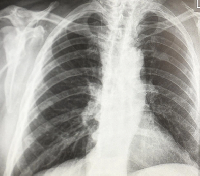

Магнитно-резонансная томография (МРТ):один из самых эффективных методов диагностики заболеваний